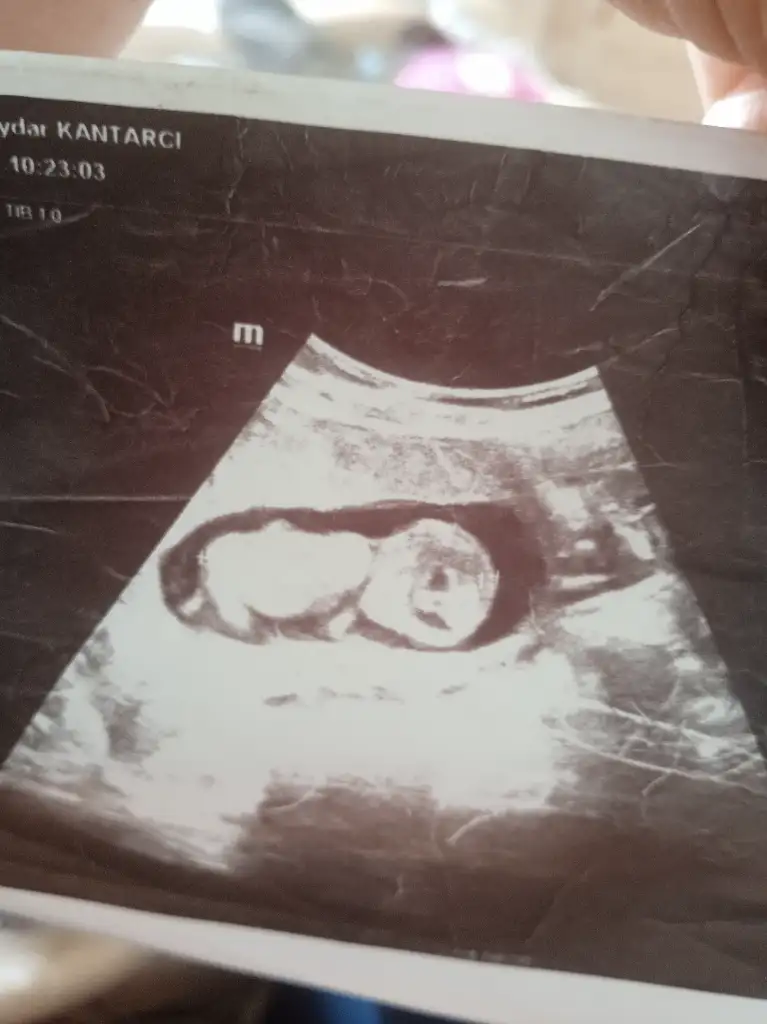

Merhaba 11 hafta 6 gün çatlamak üzereyim bana da bakabilir misiniz?Evet erkek bu bebiş

KızMerhaba 11 hafta 6 gün çatlamak üzereyim bana da bakabilir misiniz?